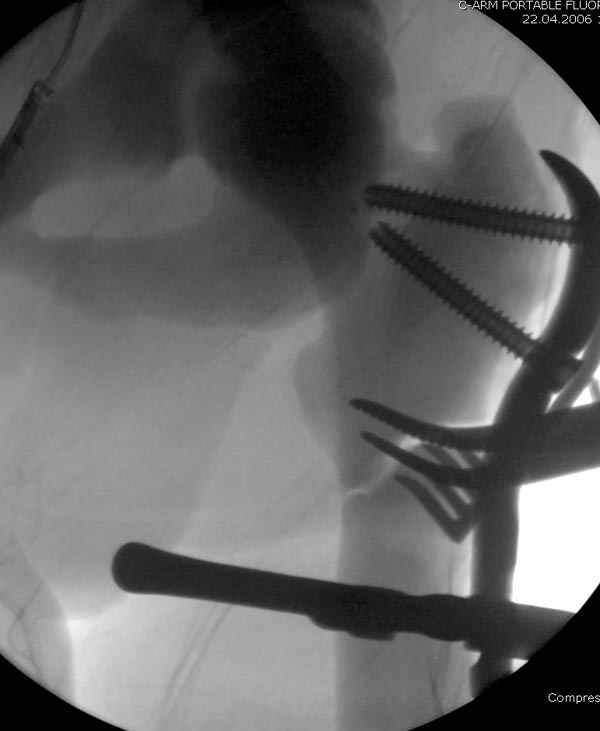

После неудачной попытки скелетного вытяжения в первом мед.учреждении, после осмотра снимков и изучения истории, поставили диагноз “Остеопетроз” или мраморная болезнь, редкая наследственная костная паталогия, где имеется нарушение формации остеокластов.

Конечно, было бы идеальным применение интрамедуллярного остеосинтеза, но учитывая прежний собственный опыт (лечил перелом бедра) и

публикации, предупреждающие о трудностях при обработке кости (иногда из-за неподготовленности инструментария результатом была неадекватная фиксация перелома, или перенос операции из-за фактора усталости оперирующего персонала), решили применить пластину (и в этом же случае был выбран Synthes plate, так что представитель за два дня

зароботал... на десерт тоже).

Заказаны были дополнительные различные дрели, и на следующий день, усиленной бригадой, больного прооперировали, потратив на каждое отверстие около 25-35 минут, хотя сверлили с охлаждением по нарастающей по диаметру сверл и с их заменой каждые 2 мм сверления.

Теперь стоит задача со сращением перелома, из-за отсутствия литературных данных по применению костных стимуляторов при остеопетрозе, и не зная как поведет в этой среде Grafton, все таки надеюсь, что даст толчок к стимуляцию, решил применить пастообразную деминерализованную костную матрицу, расположив спереди между отломками.